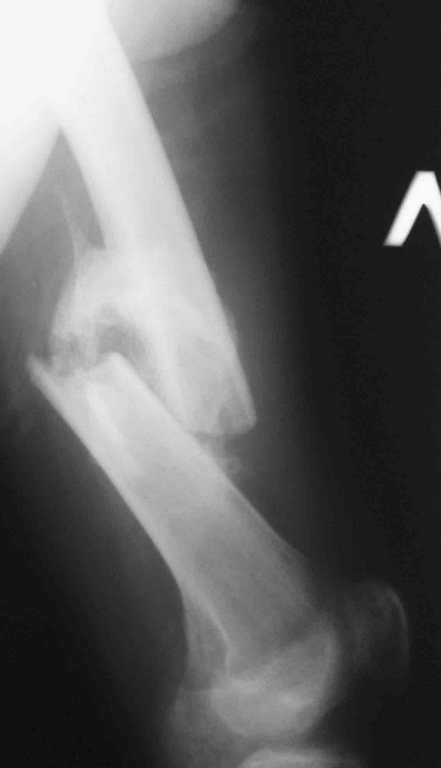

Re: 32- летний пациент с переломами обоих бедер после неудачного оперативного и консервативного лечения.

Иллюстрации к сообщению

Вышеизложенная ситуация Вами не столь трагична, если бы в Вашем арсенале использовался метод чрескостного остеосинтеза в комбинации с интрамедуллярным остеосинтезом с блокированием. В данной ситуации (справа)удаление стержня ЦИТО можно совместиь с остеотомией/кортикотомией на вершине деформации с наложением дистракционного аппарата с последующим исправлением деформации и длины сегмента, а вторым этапом ЗИО. В отношении другого бедра ситуация анологичная, только без удаления металла. Если подобные методики у Вас не используются, сочувствую!

Уважаемый Антон.Исходя из Вашего материального положения!! и наличия хорошего, грубого омозоления, равности длины конечностей и судя по снимкам не очень выраженной антекурвации, но выраженной контрактуры коленных суставов: чтоб не упустить время разработки суставов и активизировать больного, необходимо справа удалить стержень, рассверлить канал и произвести ЗИМО более толстым неблокир. стержнем т.к. на этом уровне можно получить устойчивый остеосинтез, после чего активизировать и дозированная, упорная ЛФК, а дальше после восстановления функции ,время покажеть.

Cyдя по представленным рентгенограммам оба бедра консолидированы. Необходима активная разработка движений в коленных суставах. Хотелось бы увидеть фотоснимки больного ( нижних конечностей спереди и сбоку). Если стержень мешает разработке движений то его надо удалить.

О происхождении такого запущенного случая- мой коллега работает экспертом ВТЭК и тянет в отделении и не такие казусы. Сегодня была сделана операция удален стержень из бедра и установлен стержневой аппарат из 2 опор, слева подвижности не наблюдалось, продолжается ЛФК. При необходимости позднее будет выполнена надмыщелковая корригирующая остеотомия. Спасибо всем за советы.